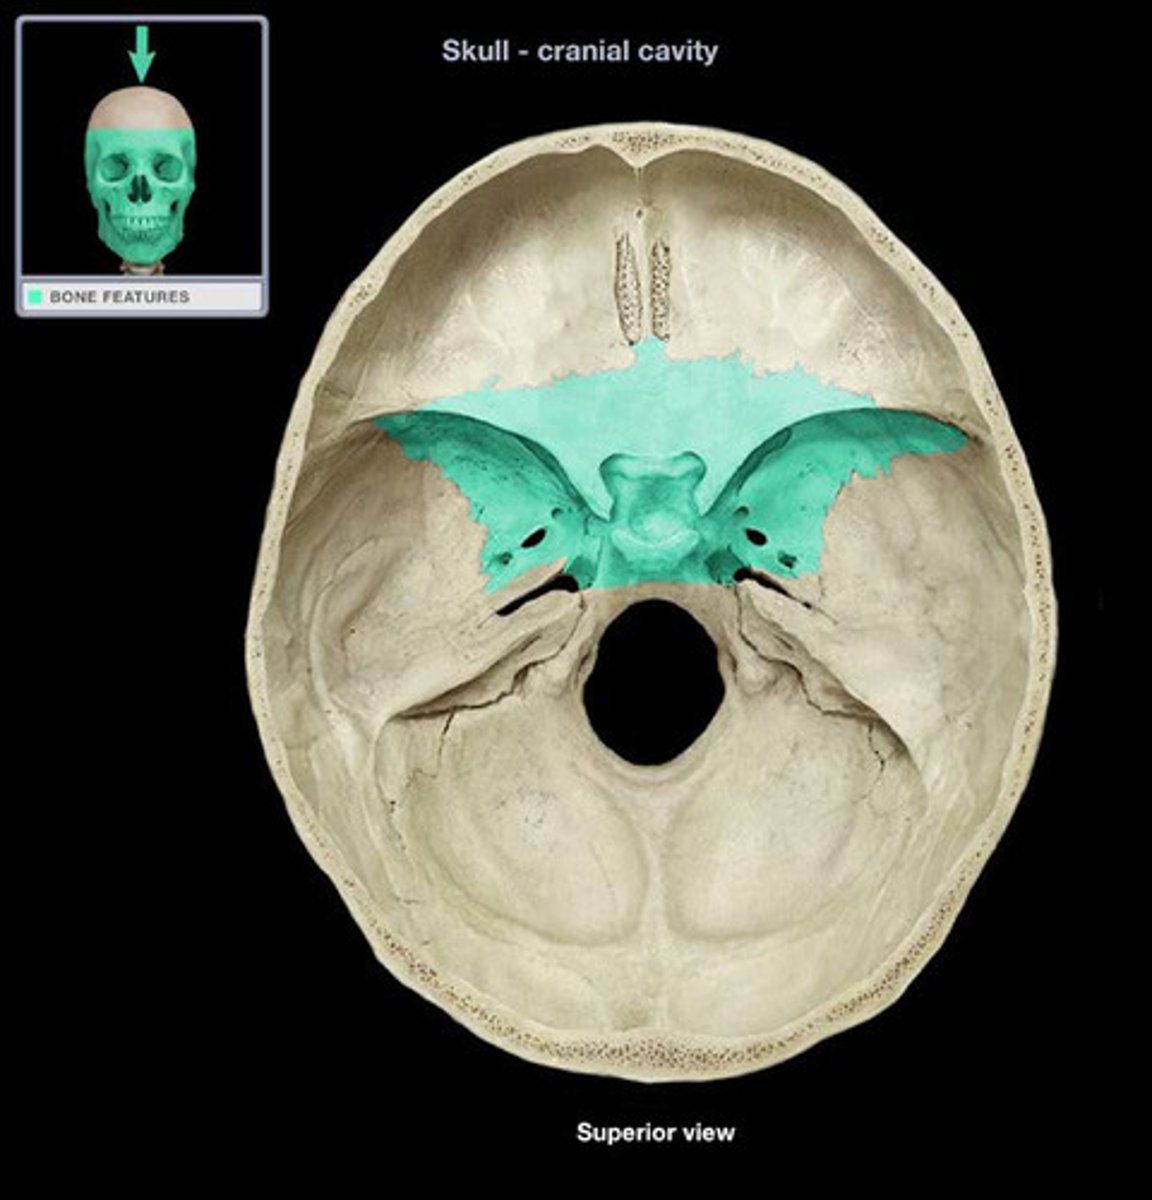

Sphenoid

Sphenoid

Sphenoid

Sphenoid

Pituitary Fossa

Ethmoid Bone

Ethmoid Bone

Cribiform Plate

Optic foramen